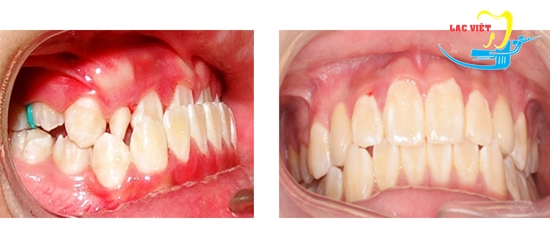

Niềng răng là phương pháp chỉnh móm mang lại hiệu quả tối ưu nhất

3. Hình ảnh trước và sau khi niềng răng móm tại nha khoa Lạc Việt

Một vài hình ảnh trước và sau khi niềng răng móm tại nha khoa Lạc Việt (*)

(*) Lưu ý hiệu quả khác nhau trong từng trường hợp cụ thể